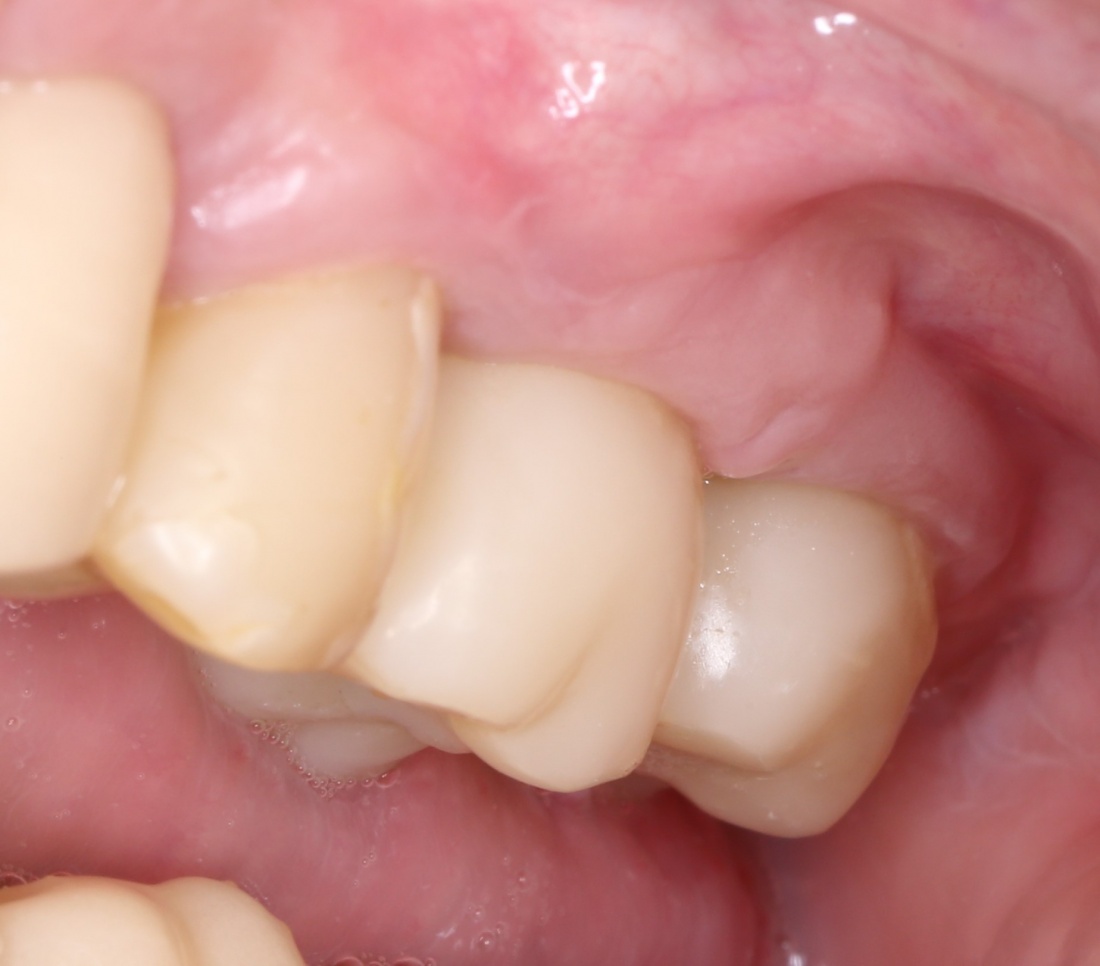

«Ого, какие классные зубы!» — сказала тогда Зинаида, после чего мы попрощались и договорились встретиться через полгода-год для замены временного протеза на постоянный керамический. Зинаида вернулась домой, в дружественную среднеазиатскую страну.

Но… в начале 2025 года я получаю от Зинаиды письмо, в котором она просит закончить лечение. Я с ужасом ожидал каких-нибудь жалоб и проблем (всё же, 11 лет без наблюдения стоматолога), но оказалось, что Зинаида просит поменять износившиеся временные коронки на постоянные. Да-да, ты не ослышался! Она 11 лет пользовалась временными коронками, и всё, что её беспокоит — это износ временных коронок!. Это абсолютный рекорд, я считаю.

И КЛКТ показала нам, что с имплантатами и окружающей костью всё зашибись. Через 12 лет после операции, отсутствия наблюдения, пофигизма в замене временных коронок! Нужны ли тебе еще какие-нибудь доводы в пользу долгосрочной эффективности метода?

А дальше всё просто. Я попросил своего коллегу Ивана Алгазина заменить износившиеся временные коронки на постоянные керамические — но с учётом современных реалий и требований:

Вот так закончилась 12-летняя эпопея Зинаиды с восстановлением зубов на нижней челюсти. Через пару дней она уехала на экскурсию в Санкт-Петербург (на всякий случай, мы попросили задержаться в России, вдруг потребуется коррекция), а оттуда — домой, в дружественную страну. Судя по тому, что она нам пишет — у неё всё прекрасно и хорошо. Зинаида обещает не пропускать профилактические осмотры и наблюдаться у стоматолога по месту жительства.